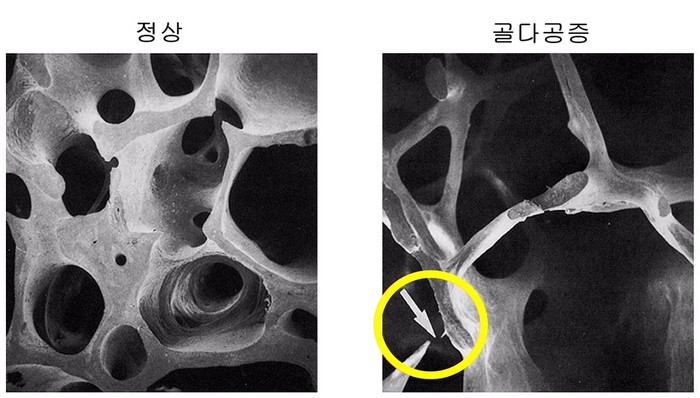

우리 몸을 지탱하는 대들보 역할을 하는 뼈는 칼슘과 인을 저장하는 역할과 함께 혈액을 생성하는 골수를 비롯해 심장, 폐 등 주요 장기를 보호하고 있다. 이러한 뼈의 강도가 약해져 쉽게 골절이 발생하는 질환을 골다공증이라고 한다.

| ▲뼈단면비교사진 [정상환자골다공증환자] |